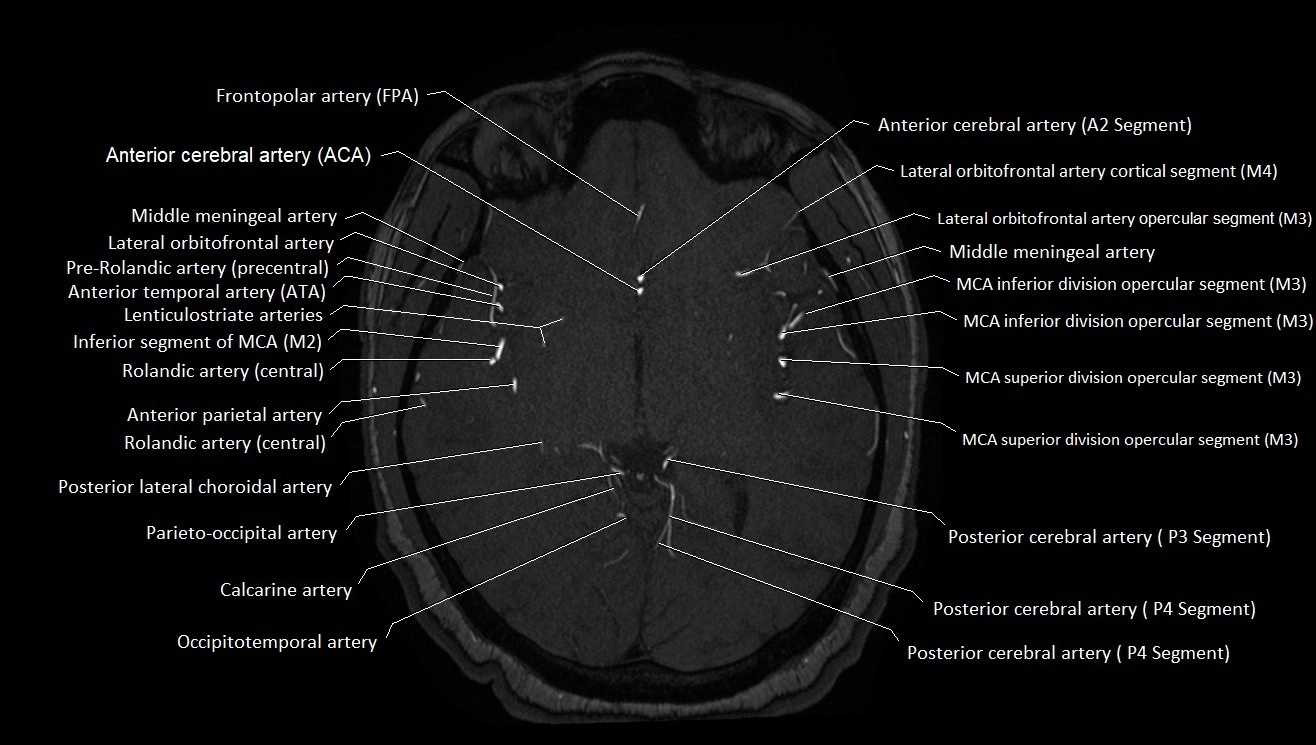

MRI images

image